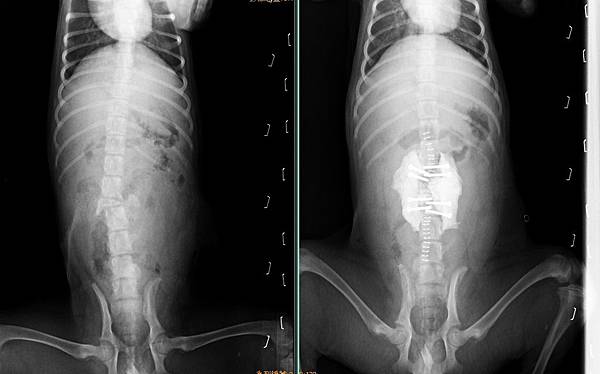

鳳梨是一位三個月大的小男孩,

被狼犬咬傷脊椎導致骨折,

拔拔麻麻從外縣市找到小譚醫師這裡尋求幫忙。

我們也在最快的時間內,

從就診到手術完成3小時完成脊椎骨折修復術。

手術過程中發現,

脊椎的第三腰椎幾乎粉碎消失,

於是我們拉開粉碎壓迫神經的骨頭並且將脊椎固定,